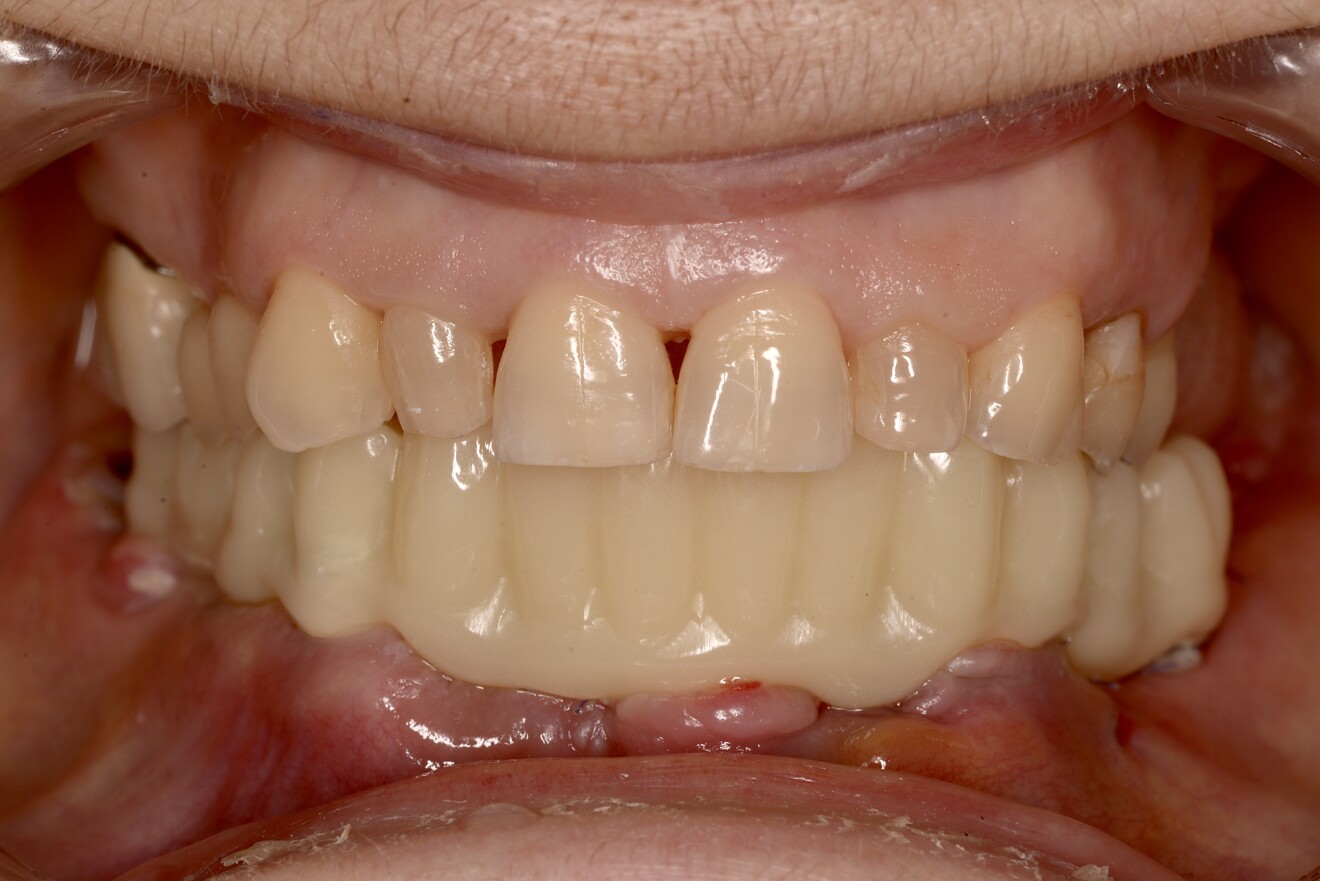

Postoperative medication consisted of a seven-day course of amoxicillin–clavulanic acid (875/125 mg, twice daily), diclofenac (50 mg, up to three times daily as needed) and a chlorhexidine mouthrinse (two to three times daily). The patient was recalled the following day for delivery of the screw-retained PMMA provisional restoration, which showed excellent passive fit and acceptable occlusion (Figs. 8a & b).

Fig. 8b: Delivery of the provisional restoration the day after the surgery.